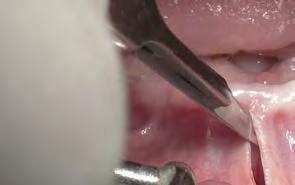

Para los autores Márcio Fernando de Moraes Grisi y Daniela Correa Grisi, las cirugías y técnicas mínimamente invasivas deben ser tomadas como procedimientos de rutina, ya que producen menos molestias, menos complicaciones posquirúrgicas y un máximo bienestar del paciente. No obstante, los doctores Moraes Grisi y Correa Grisi han querido desmitificar la idea de que la realización de los procedimientos mínimamente invasivos solo pueden hacerse con el uso de equipos extremadamente sofisticados.

Ante estas premisas, los autores idearon un atlas dedicado específicamente a los procedimientos periodontales mínimamente invasivos. A lo largo de sus 22 capítulos encontramos desde cómo trabajar con lupas prismáticas, microscopios y todo tipo de instrumental, hasta la presentación del paso a paso de las diferentes técnicas no quirúrgicas y quirúrgicas mínimamente invasivas. Los autores han buscado en cada técnica su comparativa con las técnicas convencionales, apoyándose siempre en las evidencias científicas más recientes.